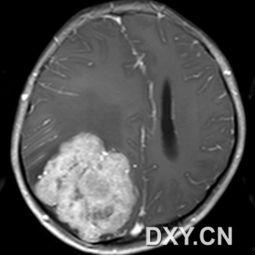

你有没有想过,当你打开电脑或手机,浏览网页时,那些神秘的脑肿瘤图片究竟是什么样子呢?今天,就让我带你一起揭开这些神秘面纱,从多个角度来探索这些令人敬畏的医学影像。一、脑肿瘤的起源首先,让我们来了解一下什么是脑肿瘤。脑肿瘤是指发生在脑部或神经组织的异常细胞群。这些细胞不受正常生长控制,可能会形成肿块,压迫周围组织,影响脑功能。据统计,全球每年约有50万人被诊断出患有脑肿瘤。二、脑肿瘤的类型脑肿瘤可以分为良性和恶性两大类。良性肿瘤生长缓慢,边界清晰,通常不会侵犯周围组织。而恶性肿瘤则生长迅速,边界模糊,容易侵犯周围组织,甚至转移到其他部位。1. 良性脑肿瘤:...